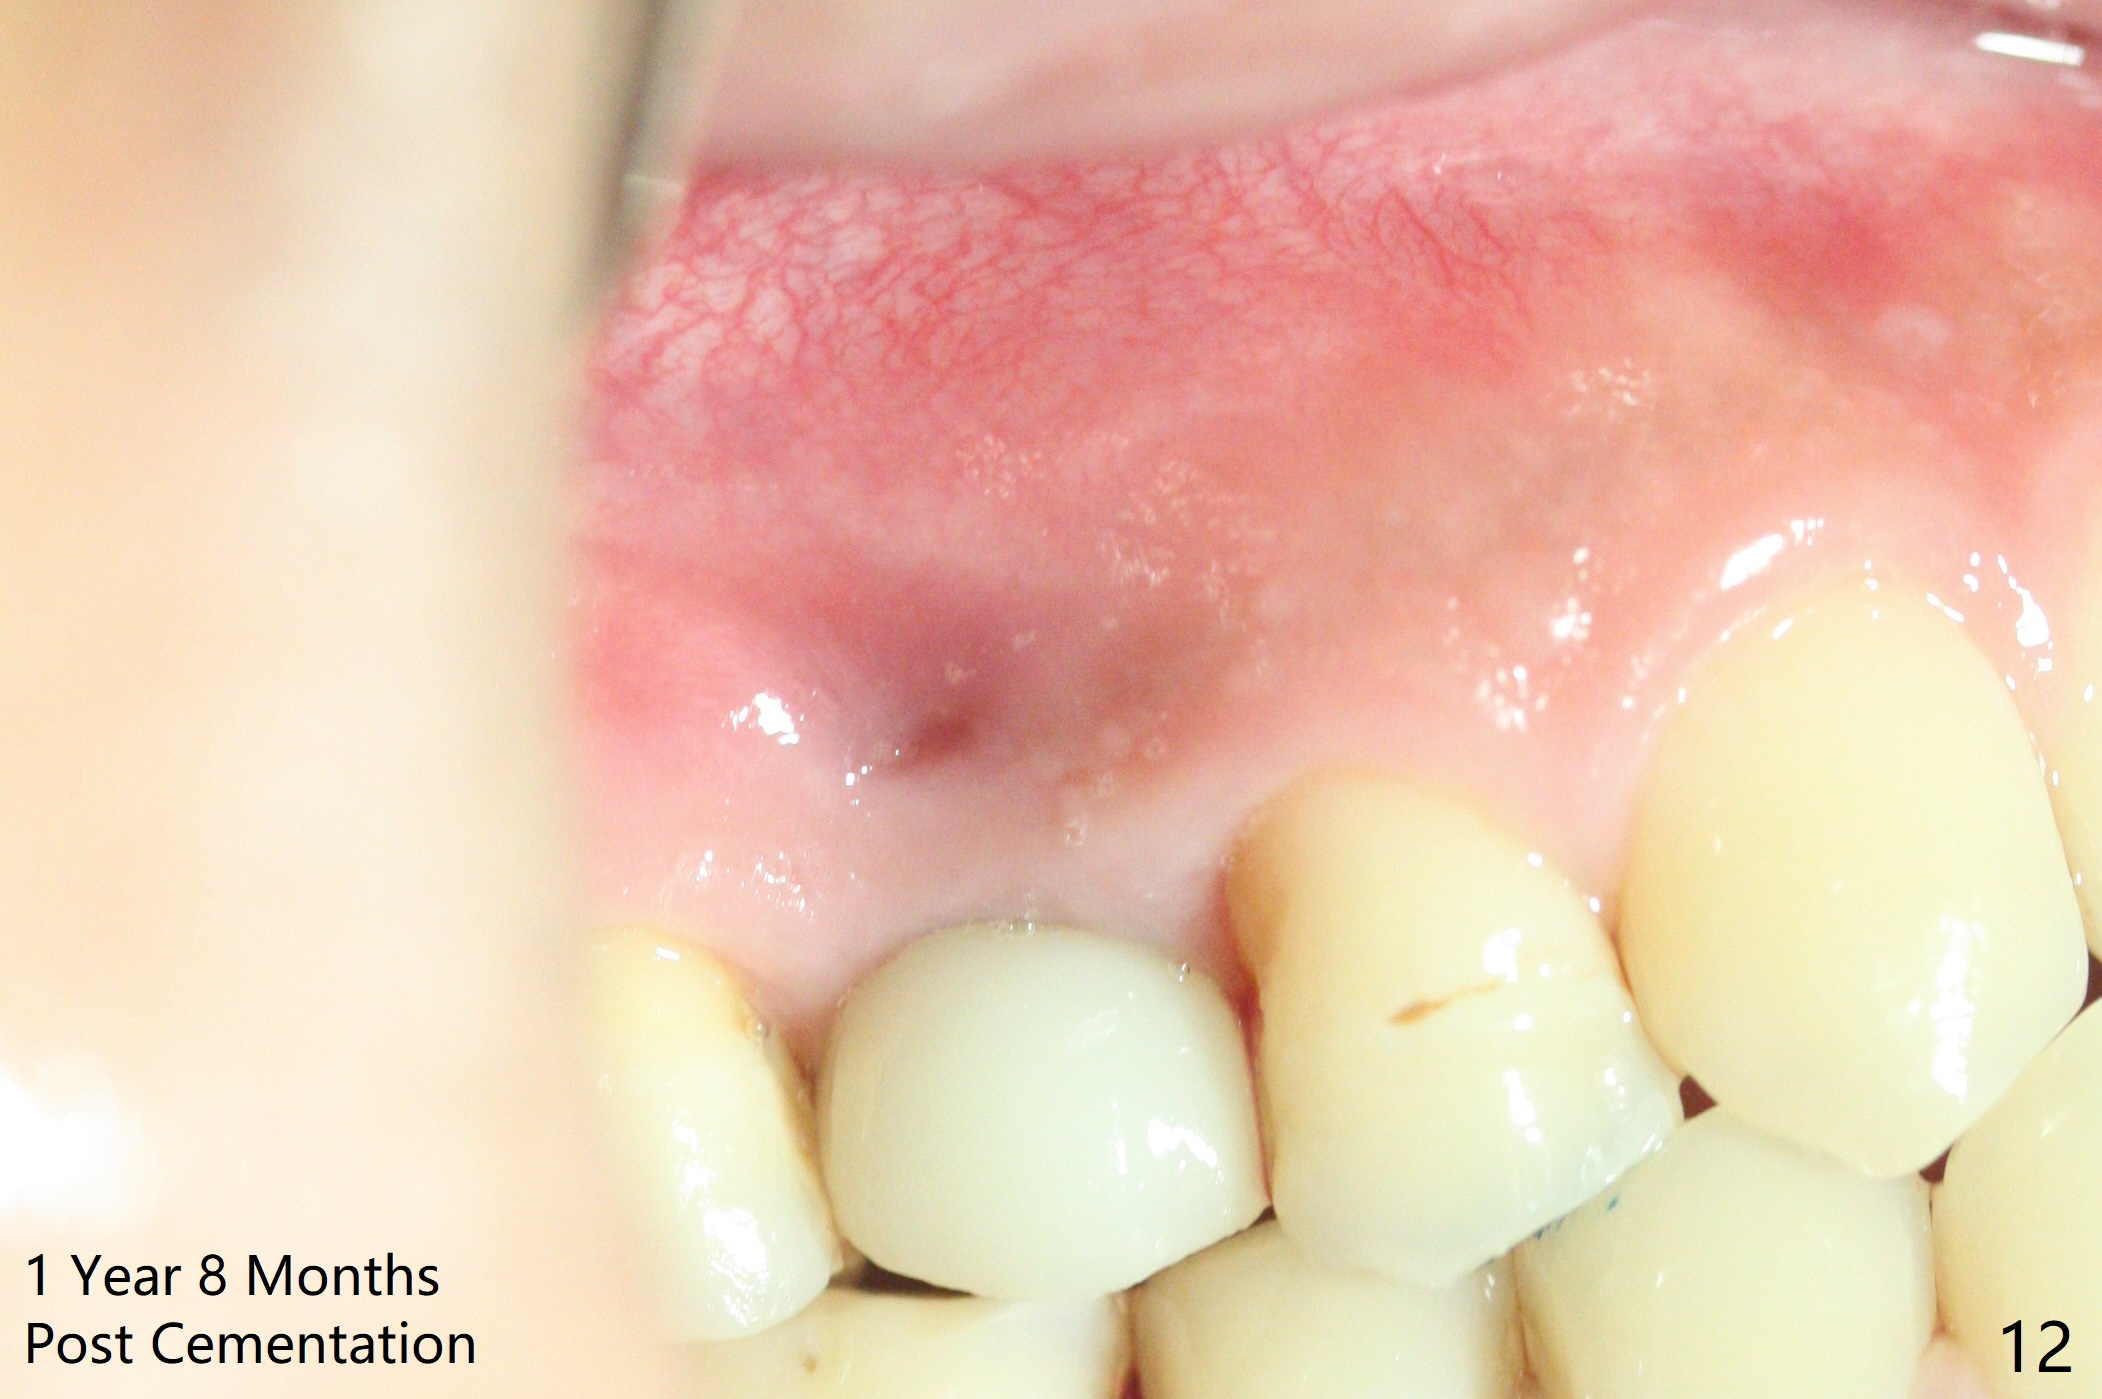

In fact there is a small buccal fistula, which is communicated with the underlying implant threads. Although preop CT shows that the buccal crest is lower than the palatal (3.8x13 mm, Fig.10 P) one, intraop finding of missing buccal plate should dictate a shorter implant (Fig.11) or onlay graft to avoid periimplantitis. Regeneration of the bone plate is limited. Later the fistula disappears with formation of a concavity (Fig.13). There is no symptom. Is bone graft necessary with a remote incision? 3-D images of CT taken 1 year 5 months post cementation show possible mesiobuccal and distopalatal bony defects (Fig.13-16). It is possible that bone graft was placed enough palatal (Fig.16). DO composite at #3 is redo satisfactorily (Fig.17 *).